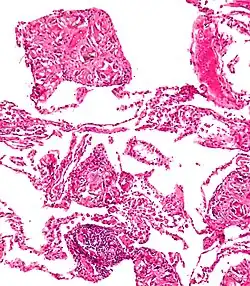

| An endoscopy image of the stomach, showing a foreign body in the form of a swallowed toothbrush. | |

One of the most common locations for a foreign body is the alimentary tract.

It is possible for foreign bodies to enter the tract from the mouth or rectum.